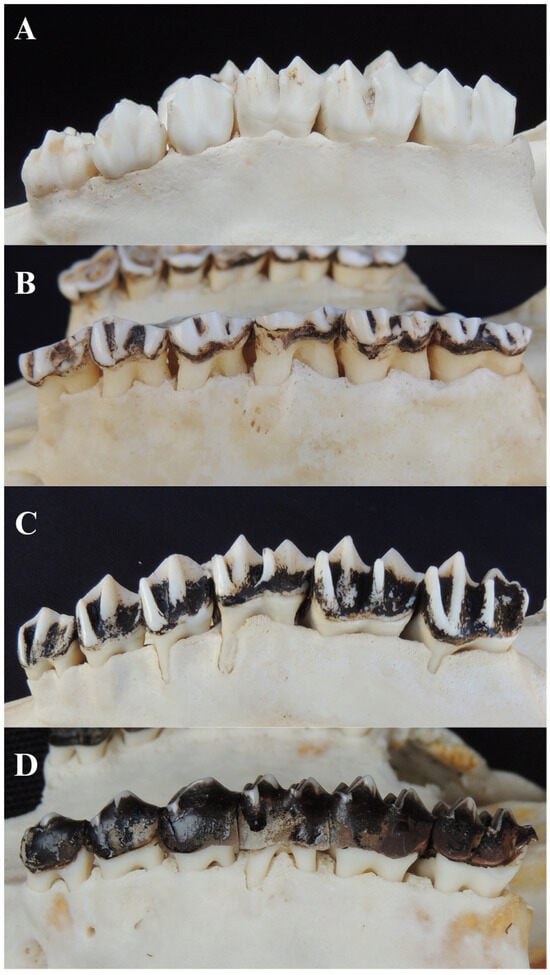

3.5.1. Dental Calculus

3.5.2. Tooth Wear and Dentine Exposure

3.5.3. Tooth Loss

3.5.5. Tooth Fracture

3.5.6. Furcation Exposure